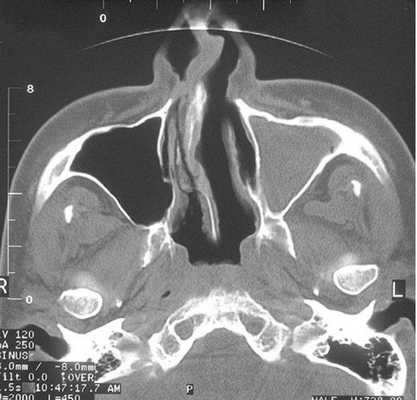

Тотальное заполнение жидкостью (кровью?) левой верхнечелюстной пазухи, повреждение носовой перегородки на компьютерной томограмме

Компьютерная томограмма носовых пазух: правосторонний гайморит